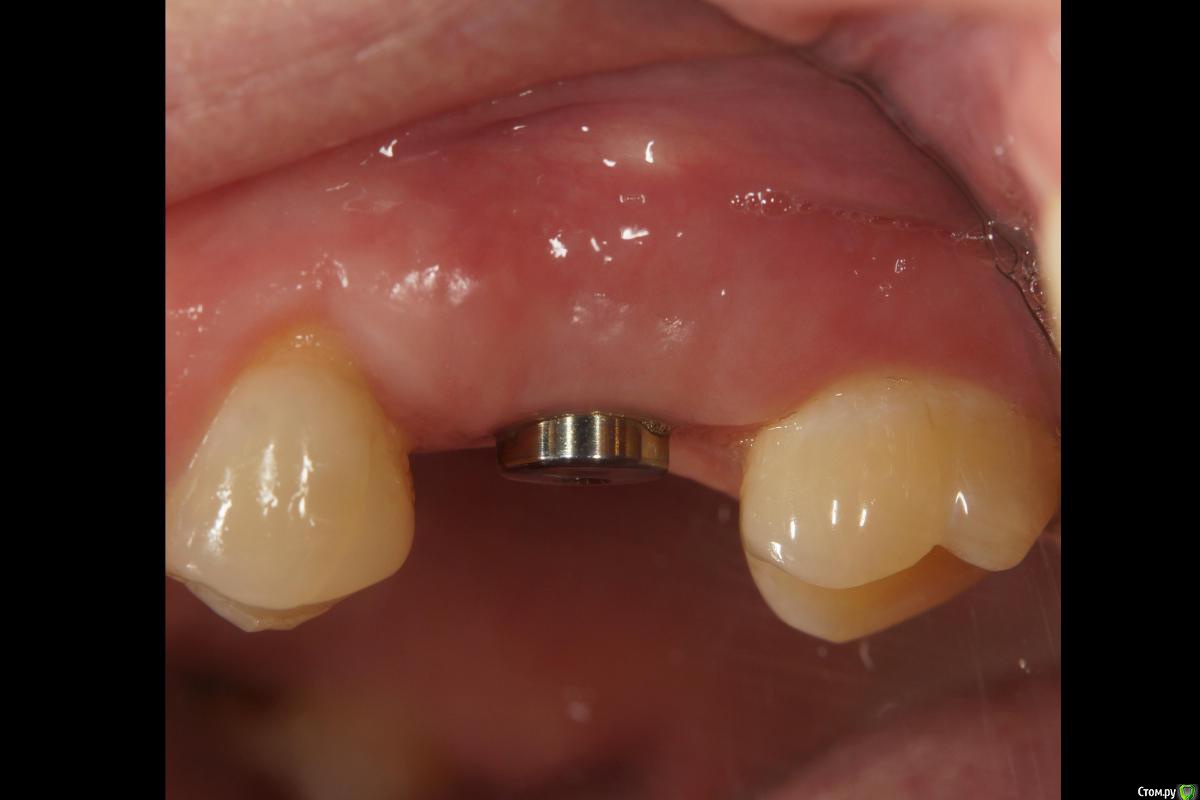

Мой первый туннель выглядел так. Начиналось все обыденной имплантацией мис С1, не хотел совмещать с мягкотканной т к мисы стабильно выпадали в то время. Меньше рисков.

Через четыре месяца проверил торк и пошел шить. Забор отсюда же, сейчас взял бы с бугра, но не жалею - паралельно замастерил рецессию.

Ещё через две недели (на снятии швов) просто облепили напару с ортопедом формик жидким и "индивидуализировали" его.

Месяц с копейками прошел, ждём протезирования. Пациентка затягивает уже три месяца на данный момент, финансы. В этом смысле особо приятно, что аугментация и индивидуализация обошлись в 0 руб. 0 коп.